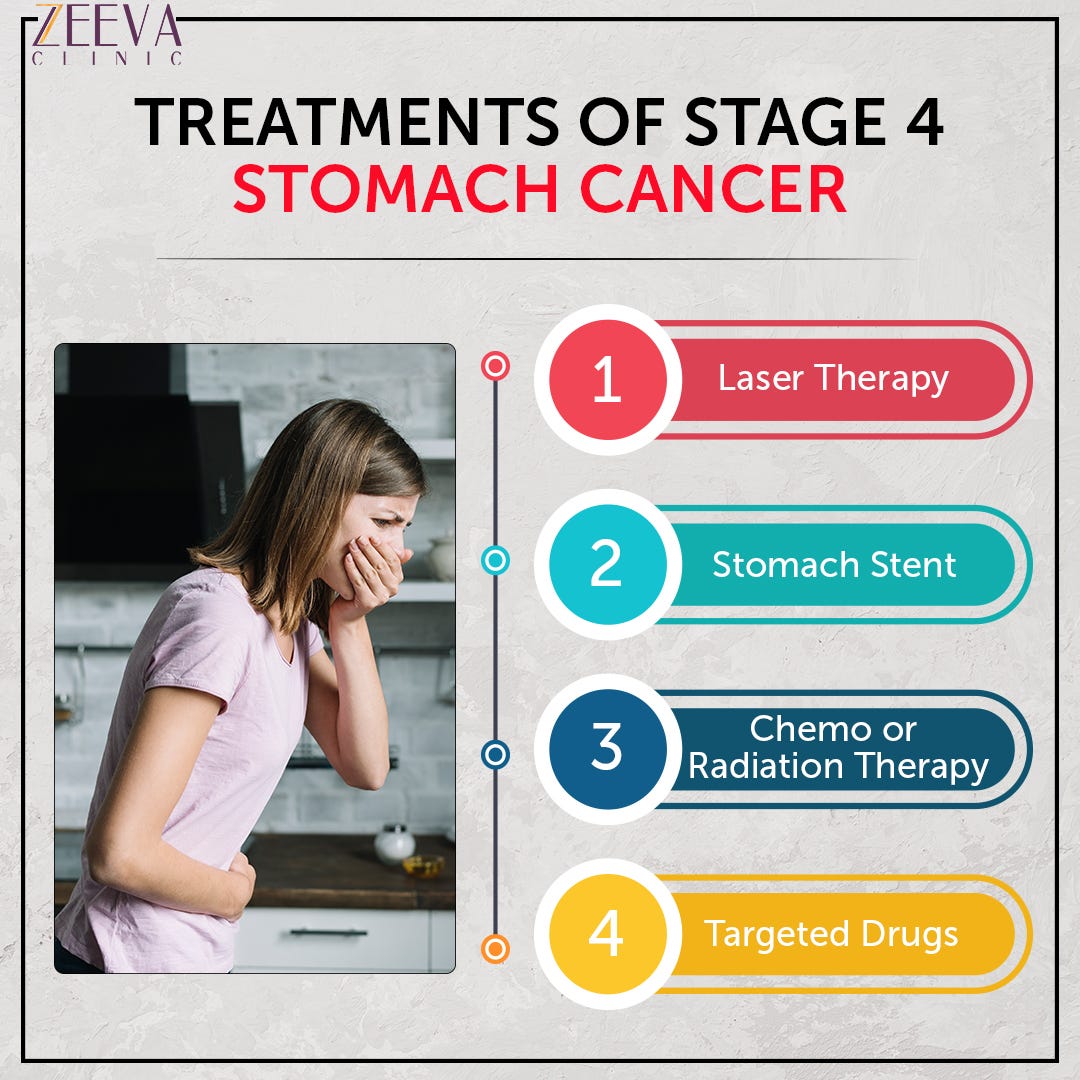

Stage 4 Stomach Cancer. What is advanced cancer? | by Zeeva Clinic | Medium

Stage 4 Stomach Cancer. What is advanced cancer? | by Zeeva Clinic | Medium

Stage 4 Stomach Cancer. What is advanced cancer? | by Zeeva Clinic | Medium